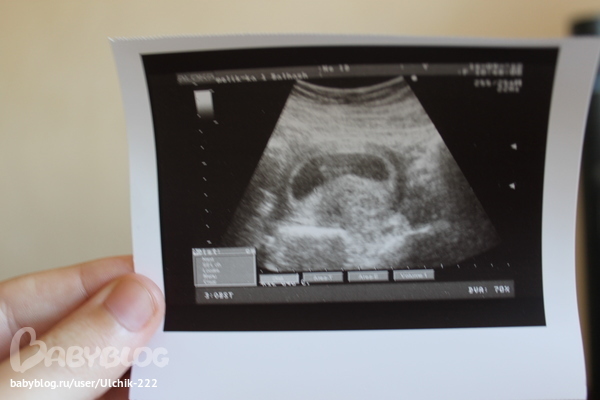

ВОТ ТАКИЕ МЫ!!!))))) Делюсь радостью)))

УЗИ, КТГ, доплерУтро началось прекрасно)))) смотрели с мужем на нашу ляку))))

А теперь подробности))))) плодное яйцо расположено в матке,средневнутренний диаметр 60 мм,соответствует 9 неделям, эмбрион ктр 23 мм, соответствует 9 неделям, сердцебиение +, желточный мешочек визуализируется, воротниковое пространство без особенностей,область придатков без особенностей,плодное яйцо по задней стенке матки,заключение: беременность 9 недель. Врач сказала, что срок по размерам плода поставила, т.е.от зачатия) а по акушерским у нас сегодня 9 недель 4 дня, а со дня О 7 недель 1 день))) вот такие мы большие)))) это так крутооо) в прошлый раз мы тоже опережали свой срок от зачатия) так же,как и в этот раз))) такая узистка хорошая,повернула нам с мужем монитор, все показала,рассказала подробно) показала сердечко))) так здорово бьется))) наша ляка такая милая)))))блииин)) не испытывала я таких ощущений никогда))) еле сдержалась,чтобы не разреветься)))) но лыба с лица не сходила))) муж замер)))) классное утро)))) всех целую,всех люблю))) анализы сдавали в 6 недель после овуляции- хгч 123071,прогестерон -24.01...прогестерон это пипец конечно(((( был 37 на 5 неделе( ну что начала дюф пить по 2 табл.в день, и утрожестан 200 на ночь вагинально...сегодня БТ поднялась на градус,посмотрим,что завтра будет) а так ничего не беспокоит,ттт)) от этого прогика и на узи в ускоренном порядке побежали.)))) врач сказала,что отлично,а прогик может быть моей индивидуальной особенностью...ну посмотрим))) через недельку буду в краснодаре,пойду на учет вставать, че они мне там скажут по этому поводу)) я сама знаю девочки ,что прогик низкий,но вот ничего же не беспокоит меня и малыш развивается отлично))) с динамикой) уже была в трех разных клиниках,и говорят все что нормально все...но я вот все равно решила дюф пить...хуже не будет от него как мне кажется)))